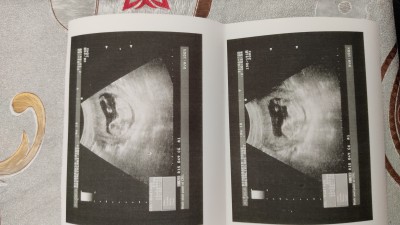

12+3 :) cinsiyeti merak ediyorum arkadaşlar ilk gebeligim Allah sağlıkla sıhhatle kucağıma almayi nasip etsin (hepimizinkini) inşallah

Gebelik haftası 12+3

Kiza benzettim ben